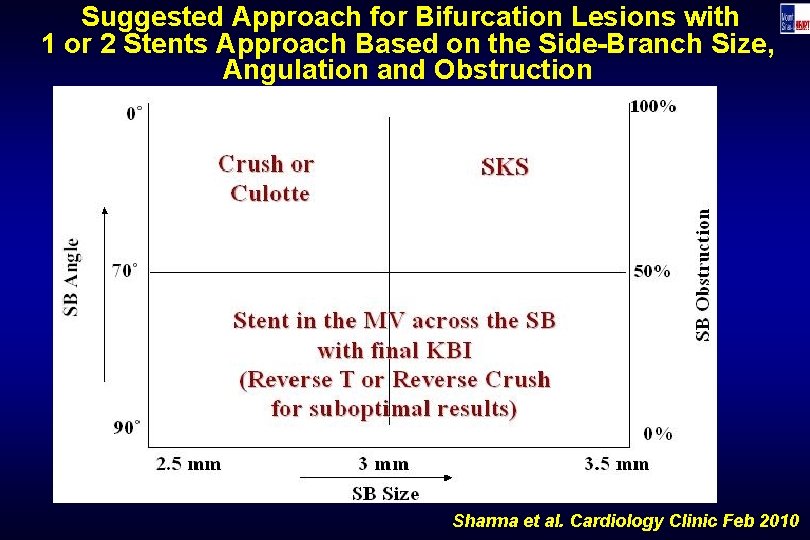

Suggested Approach for Bifurcation Lesions with 1 or 2 Stents Approach Based on the Side-Branch Size, Angulation and Obstruction Sharma et al. Cardiology Clinic Feb 2010